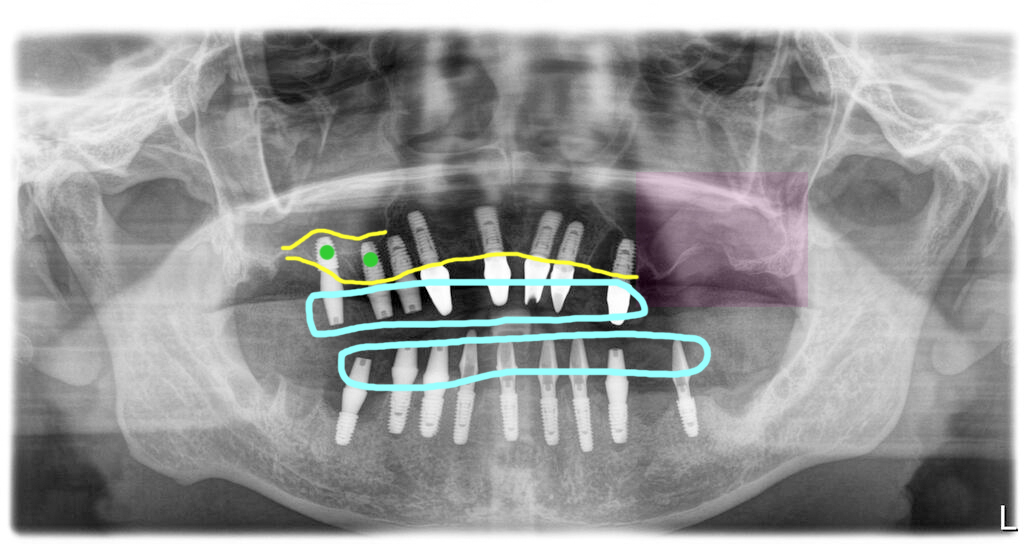

상악동 뼈이식 후 6개월 임플란트 식립

윈도우 방식의 상악동 거상술을 하더라도 상악동 바닥의 뼈가 어느 정도만 있어도 뼈이식과 함께 임플란트를 심는 경우가 더 많습니다.

하지만 이 환자분의 경우 발치 시기가 너무 늦어졌기 때문에 상악동바닥에 남은 뼈가 전혀 없어서 이렇게 긴 시간의 치료가 필요하게 되었습니다.

상악동거상술 뼈이식을 한 후 6개월 기다렸다가 임플란트를 심고 다시 6개월을 기다렸다가 최종적인 보철을 완성한 모습입니다. 그렇게 해서 이 환자는 수술을 시작하고 약 1년 반 정도의 치료기간이 걸린 경우입니다. 보통 이렇게 긴 시간이 걸리는 경우는 드물지만 환자의 상태가 허락되지 않으면 이렇게 긴 시간이 필요하기도 합니다.

현재까지 환자는 정기검진을 하면서 잘 유지하고 계십니다.